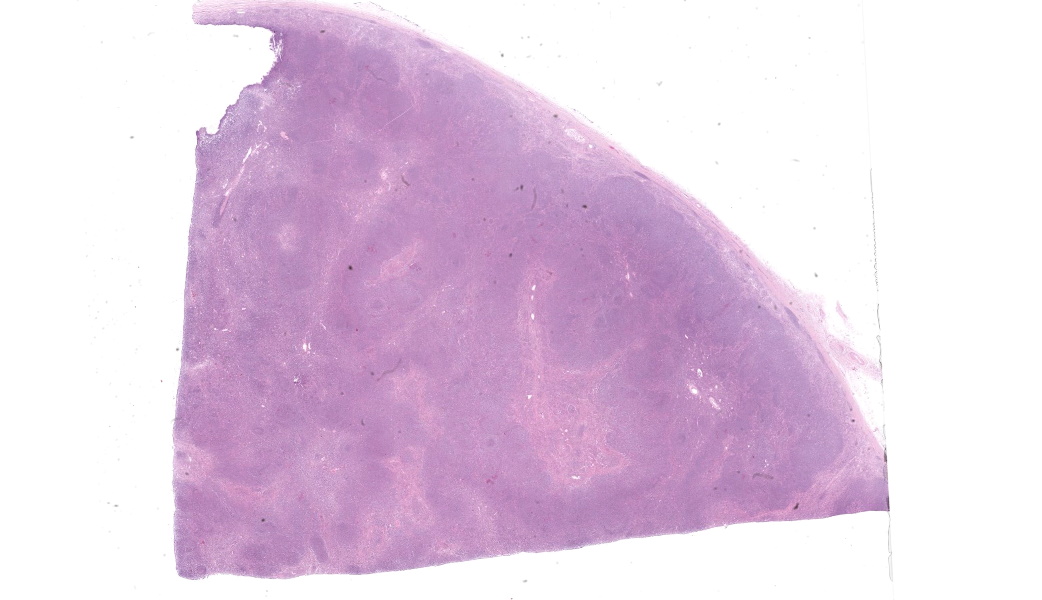

Microscopic Description:

Camel; LungDescription Multifocally throughout the section, expanding the lamina propria of larger airways, multifocally invading the airway epithelium, expanding numerous alveolar septae and infiltrating into interlobular septae and the pleural space, there is a densely cellular lymphoid neoplasm. The neoplasm is made up of sheets and rows of closely packed round cells supported by a fine pre-existing fibrous stroma. The neoplastic cells contain nuclei 5-7µm in diameter and have indistinct cytoplasmic borders, scant amphophilic cytoplasm, round to ovoid paracentral nuclei with coarsely clumped chromatin with moderate numbers of cells possessing a single nucleolus. Throughout the neoplastic cells there is mild anisokaryosis and anisocytosis. Mitotic figures numbering 5 per 2.37mm2 with occasional bizarre mitoses. Multifocally the neoplastic cells closely surround and infiltrate the tunica media of small blood vessels. Numerous alveolar spaces are filled with eosinophilic fibrillar material (fibrin) admixed with abundant neutrophils and foamy macrophages, while others contain large amounts of homogenous eosinophilic material (edema). Multifocally some alveolar spaces are expanded and ruptured (emphysema). Bronchioles contain moderate numbers of neutrophils and macrophages admixed with strands of hypereosinophilic fibrillar material (fibrin) with neutrophils transmigrating across the respiratory epithelium. There is occasional loss of type I pneumocytes with replacement by type II pneumocytes.

Camel; Paratracheal Lymph NodeDescription Multifocally the normal architecture of the cortex, paracortex and medulla is disrupted and replaced by a densely cellular neoplasm composed of lymphoid cells. The neoplasm is comprised of sheets of closely packed small round cells with nuclei 5-7µm in diameter. Cells are mostly round with indistinct cytoplasmic margins, scant basophilic or eosinophilic cytoplasm, high nuclear to cytoplasmic ratio, and a paracentric nucleus with coarsely clumped chromatin. There is mild anisocytosis and anisokaryosis. There is an average of 12 mitoses per 2.37mm2. Within the capsule of the lymph node there are small aggregates of neoplastic cells organized into sheets.